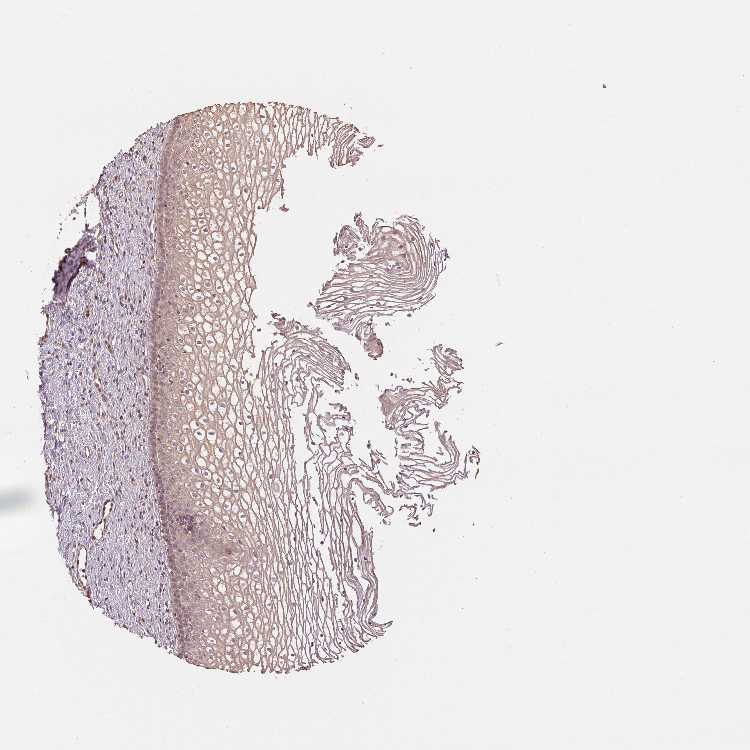

Antibody staining in the annotated cell types in the current human tissue is reported as not detected, low, medium, or high. This score is based on the staining intensity and fraction of stained cells.